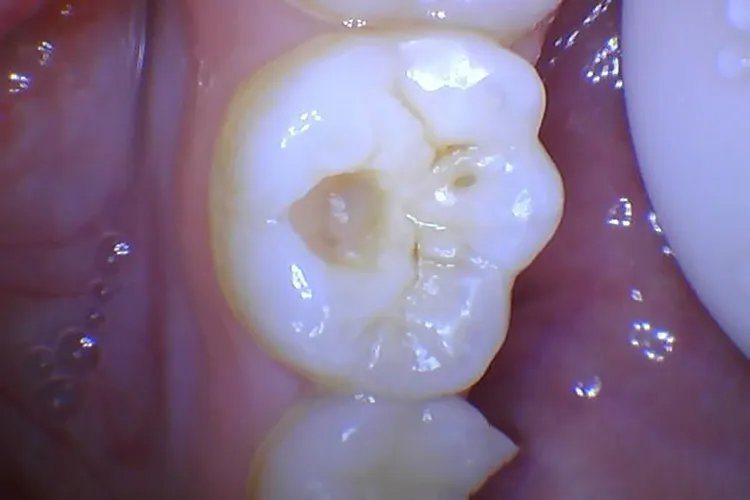

中龋中龋在检查时有明显龋洞,可有探痛,对外界刺激(如冷、热、甜、酸和食物嵌入等)可出现一过性疼痛,当剔牙或刷牙后、刺激物去除后疼痛立即消失,无自发性痛。